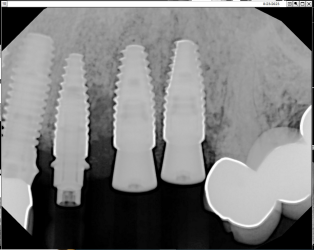

Hello,

I ran into an issue with my 81 year old Pt and thought if anyone has some insights.

This is my first implant restoration after graduation.

The implants were planned by another GP and placed by a periodontist.

#12 RC 4.1,#11 4.1 RC ,#10 3.3 NC. Straumann bone level. The periodontist placed them 6 months ago and said it is ready for…